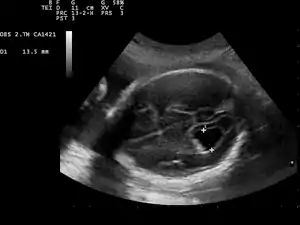

| Prenatal ultrasound showing a well defined hypoechoic lesion corresponding to a choroid plexus cyst | |